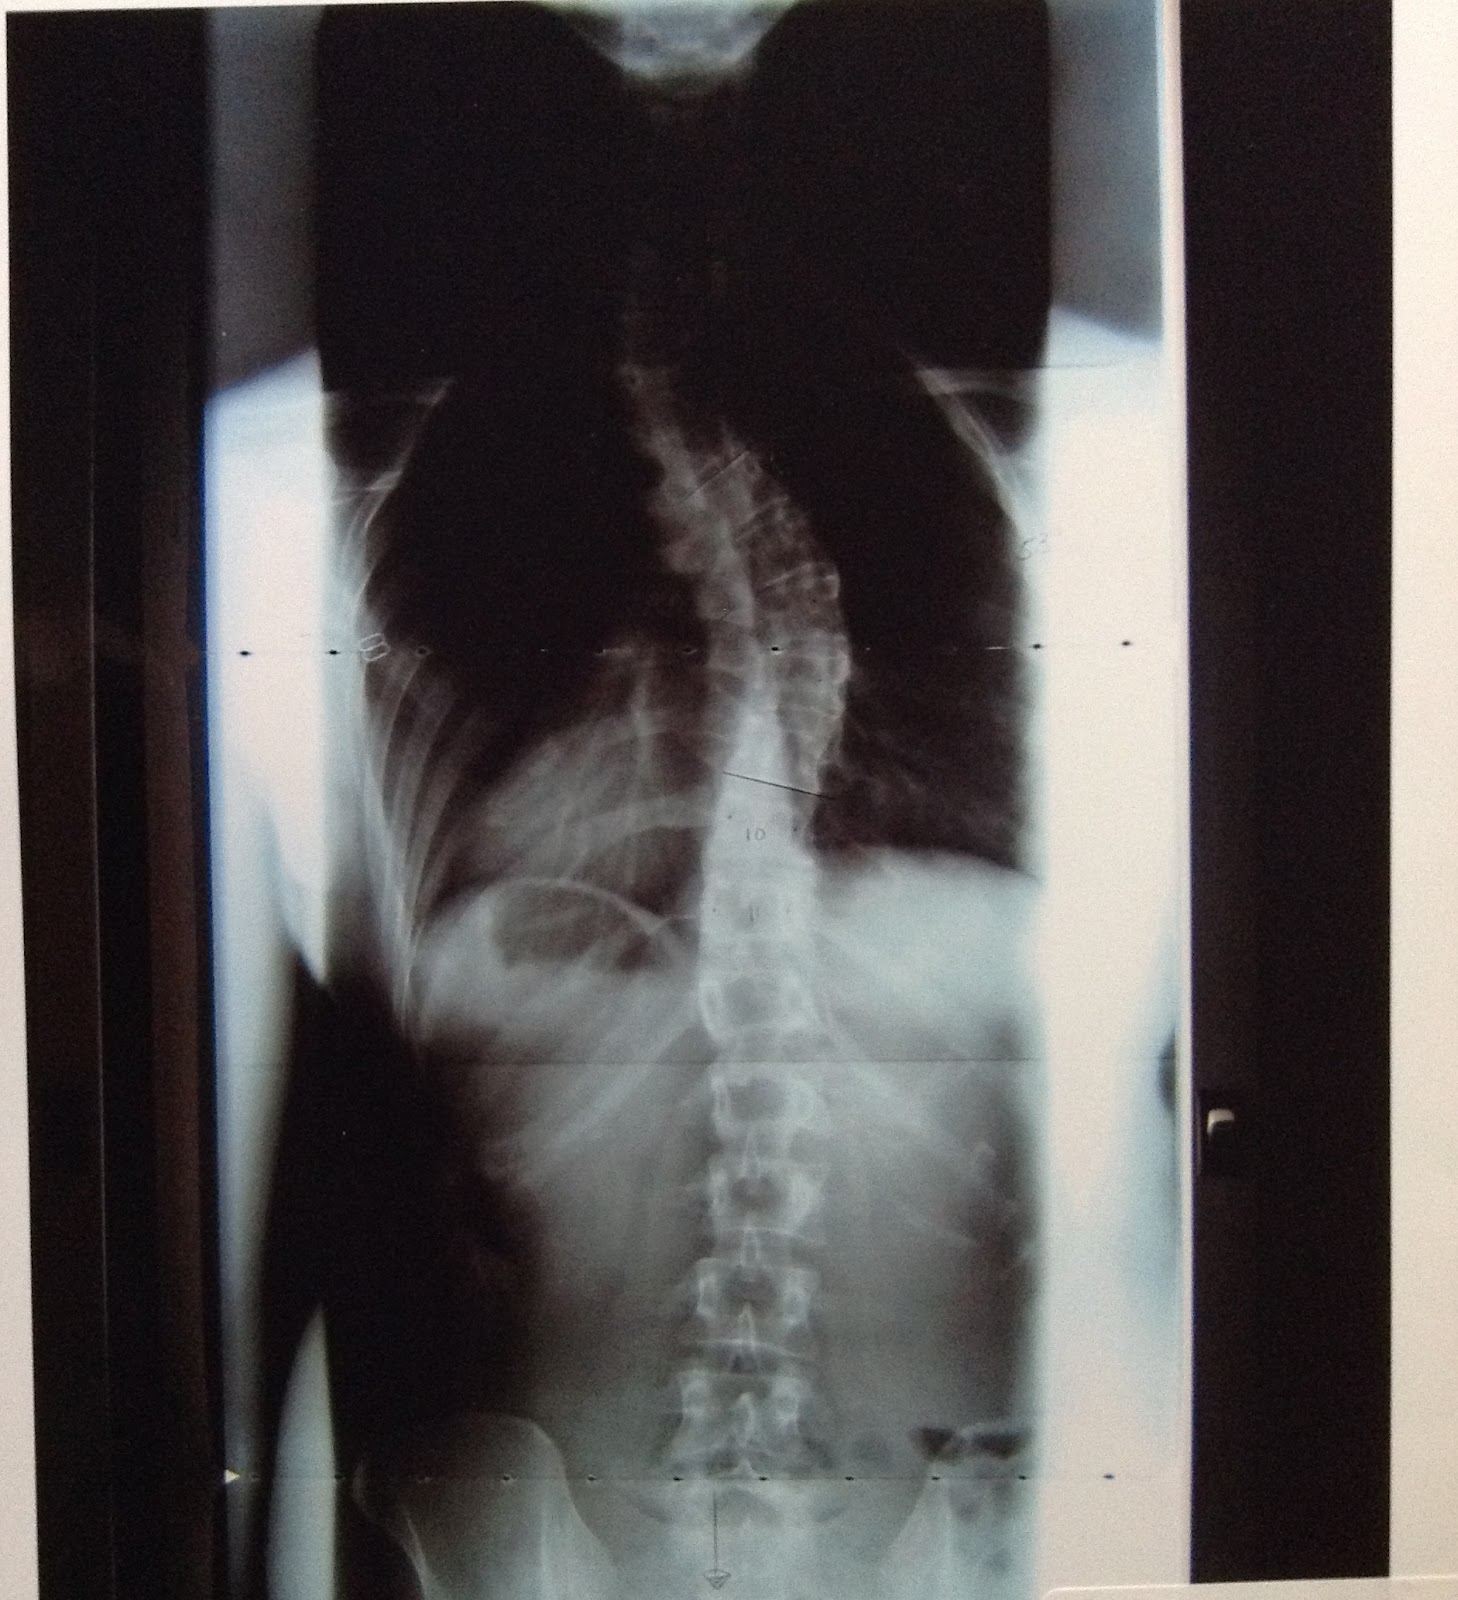

I'm very nervous about surgery tomorrow, but I know I'm in good hands. I'm expecting to be in surgery for 6-7 hours. During that time, my surgeon will make an incision on my back in the area of my thoracic spine (upper and mid-back). A combination of 35 mm screws and hooks will be attached from T2 to T11 (there are 12 thoracic vertebrae). Two 1/4-inch titanium rods will then be attached to the hooks and screws on each side of my spine. The attached rods will allow my surgeon to straighten and de-rotate my spine. Bone from my pelvis may be taken to use as bone graft to help fuse my vertebrae together. Over the past month, I donated 2 units of blood just in case I lose too much blood during surgery. My quick description of the surgery may sound simple, though it is anything but. Below are a couple x-rays showing what my spine looks like now, before surgery. My personal assistant (aka Mom), my chauffeur (aka Dad), or I will post the after x-rays as soon as possible after surgery. Hopefully there will be a dramatic difference! Now, just 8.5 hours before surgery. . .

Upper 40 degree curve

Lower 53 degree curve